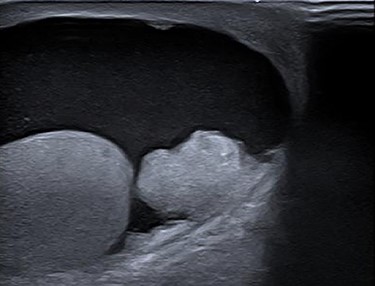

One year after surgery, his right testis was swollen and painful. There was no dysuria or hematuria. On scrotal examination, a small nodule (approximately 1 cm in diameter) was felt in his right testis. Ultrasonography showed a hydrocele of the right testis with thickening of the scrotal wall and a tumorous mass (Fig. 4). An orchiectomy was performed and pathologic analyses revealed a metastasis of the adenocarcinoma between tunica albuginea and tunica vaginalis. He started palliative chemotherapy containing capecitabine and bevacizumab. The CT scan after three cycles of chemotherapy showed a partial remission.

Ultrasonography of right testis showing hydrocele and a tumorous mass.